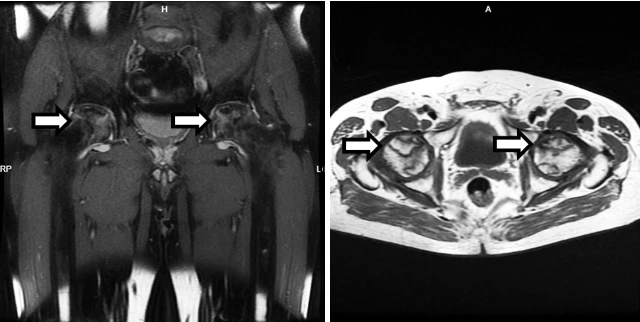

Вот такие плечики у пациента 29 лет! Во время эпидемии COVIDa-19 перенёс тяжёлую форму, лечили, в том числе, высокими дозами кортикостероидов, так что остеонекроз, который мы имеем возможность видеть в головках плечевых костей, по всей видимости, развился, как осложнение этого вида терапии. Хотя, при этой инфекции возникает ещё и гиперкоагуляция, которая и сама по себе является фактором риска развития некроза костей. В литературе такие случаи описаны и известны, есть описания развития остеонекроза даже четырёх костей одновременно (головок бедренных и плечевых костей), причём, развился он аж через полгода после окончания терапии. В нашем случае справа некроз привед к фрагментации головки плеча. Понятное дело, что функции плечевых суставов нарушены, в том числе, за счёт развития грубого вторичного артроза. Видимо, тотальная артропластика потребуется...